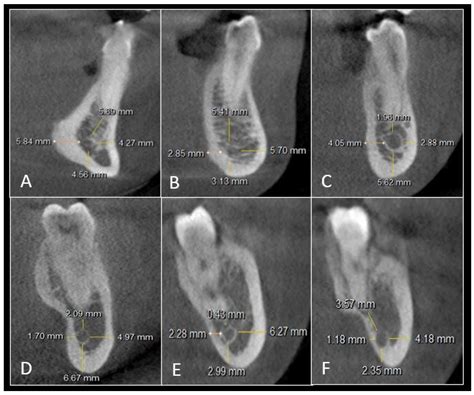

Inferior Alveolar Nerve Canal

Alveolar Process